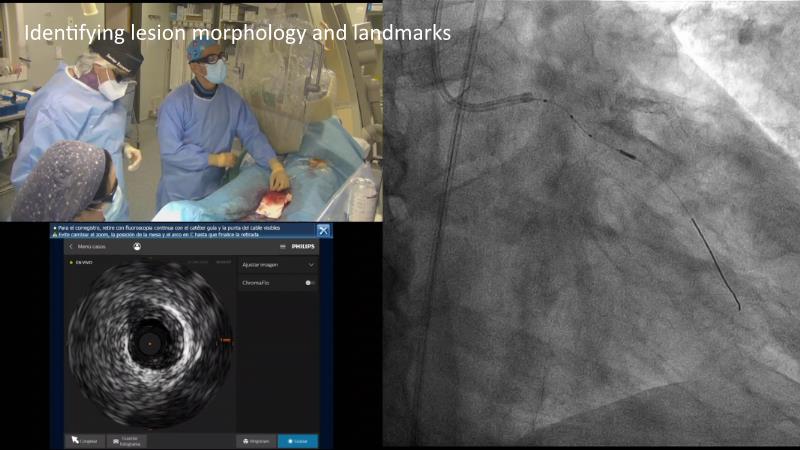

Discover the indispensable toolset of ultra-low contrast (ULC) percutaneous coronary intervention (PCI) in complex coronary interventions and higher-risk patients in this session. Gain a comprehensive understanding of how ULC PCI can enhance the safety and quality of revascularization in complex procedures and learn practical aspects from recorded cases, including specific approaches utilizing intracoronary imaging, physiology, and dedicated tools and techniques.

- To learn practical aspects from recorded ULC PCI cases, including specific approaches using intracoronary imaging, physiology and dedicated tools and techniques